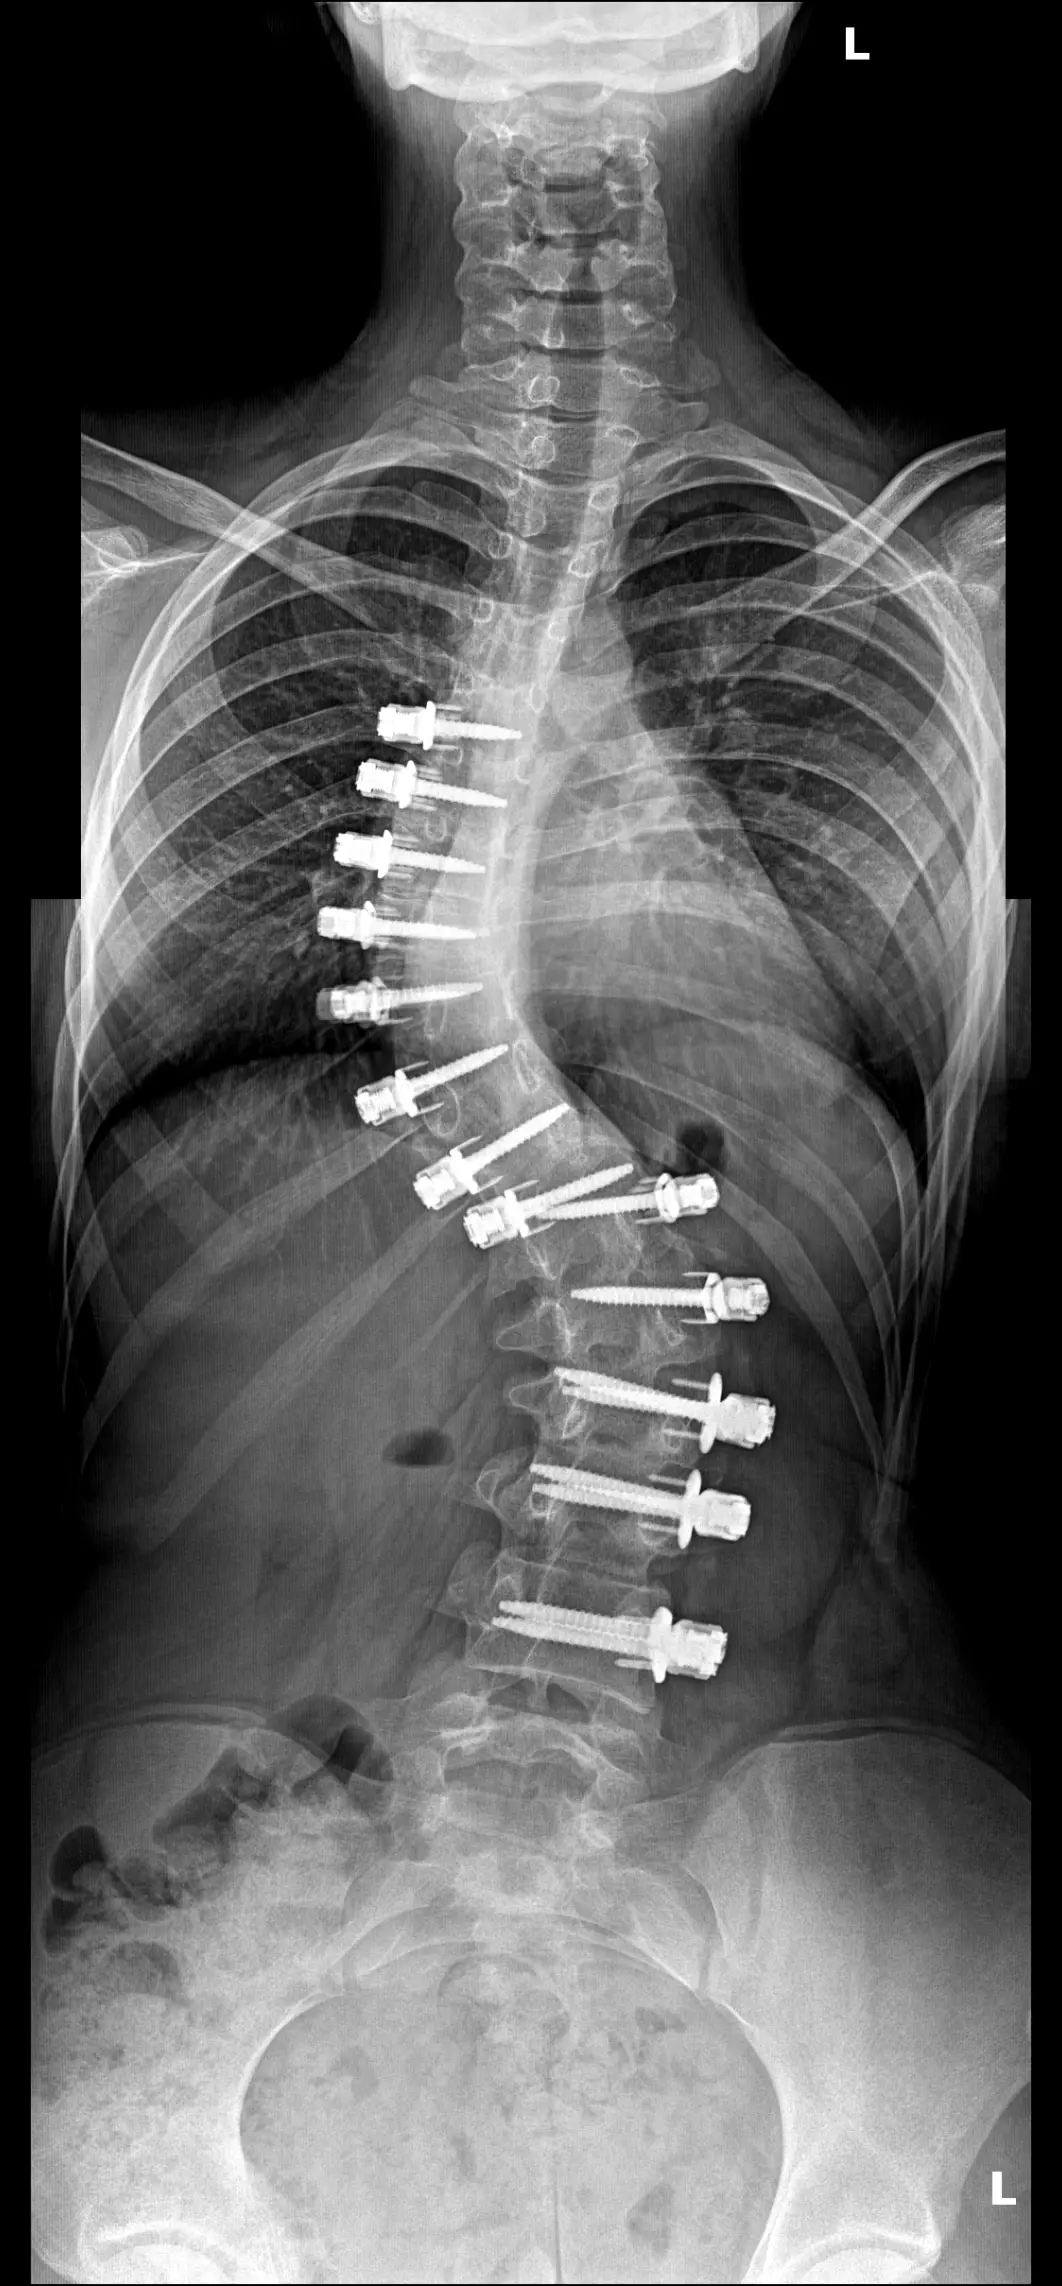

На 9 години претърпя първата си операция в Аджибадем Маслак, Истанбул, извършена от проф. Ахмед Аланай по иновативния метод VBT (Vertebral Body Tethering). За съжаление, след инцидент кордата се скъса и кошмарът започна отново – нови корсети, ново чакане.

Днес Бояна е висока 171 см, но кривината продължава да расте. На 12.11.2025 г. след пореден преглед проф. Аланай беше категоричен: без ревизионна операция състоянието ѝ ще се влошава и всичко постигнато досега ще бъде загубено.

At the age of 9 she underwent her first surgery in Ajibadem Maslak, Istanbul, performed by Prof. Ahmed Alanay under the innovative VBT (Vertebral Body Tethering) method. Unfortunately, after an accident the cord broke and the nightmare started again - new corsets, new waiting.

Today Boyana is 171 cm tall, but the curvature continues to grow. On 12.11.2025 after another examination prof. Alanay was adamant: without revision surgery, her condition will worsen and everything achieved so far will be lost.